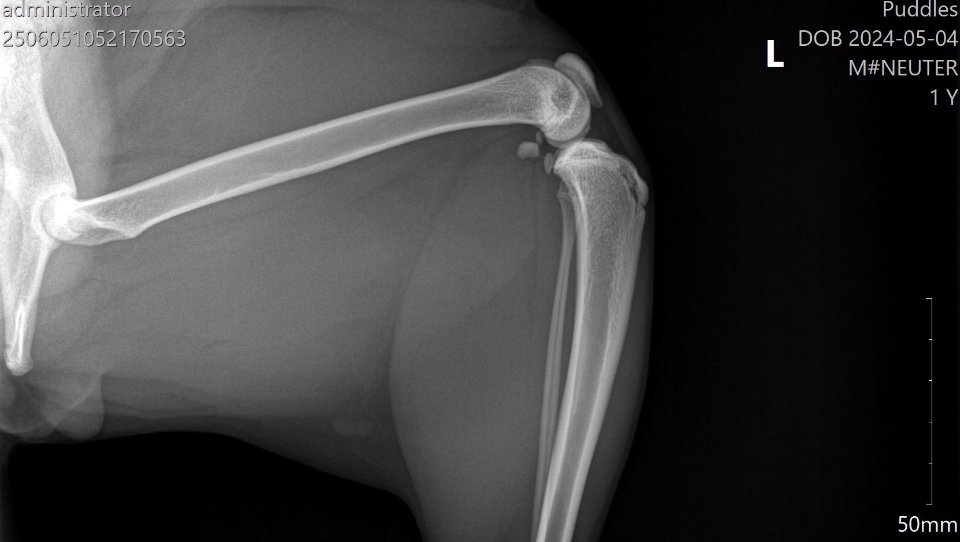

Xrays ⬇️

We rushed him to the vet the next day. That alone cost nearly $700, which completely drained us. They did X-rays and gave him pain meds, and the next day we got the news: Puddles has a fractured femur near the hip, and he needs a surgery called an FHO (femoral head ostectomy) to be able to walk normally again without pain.